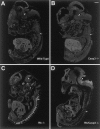

The retinoblastoma tumor suppressor protein, pRb, is a key regulator of cell cycle and has been implicated in the terminal differentiation of neuronal cells. Mice nullizygous for pRb die by embryonic day 14.5 from hematopoietic and neurological defects attributed to failed differentiation (Clarke et al., 1992; Jacks et al., 1992; Lee et al., 1992). Previous studies by MacLeod et al. (1996) have demonstrated that the loss of p53 protects Rb-deficient CNS neurons but not peripheral nervous system (PNS) neurons from cell death. Thus, the mechanisms by which PNS neurons undergo apoptosis in response to Rb deficiency remain unknown. In view of the pivotal role of caspase 3 in the regulation of neuronal apoptosis during development, we examined its function in the execution of the wide-spread neuronal cell death induced by Rb deficiency. Our results support a number of conclusions. First, we show that caspase 3 becomes activated in all neuronal populations undergoing apoptosis. Second, caspase 3 deficiency does not extend the life span of Rb null embryos, because double null mutants exhibit high rates of liver apoptosis resulting in erythropoietic failure. Third, Rb/caspase 3 double-mutant neurons of the CNS exhibit widespread apoptosis similar to that seen in Rb mutants alone; thus caspase 3 deficiency does not protect this population from apoptosis. Finally, in contrast to the CNS, neurons of the PNS including those comprising the trigeminal ganglia and the dorsal root ganglia are protected from apoptosis in Rb/caspase 3 double-mutant embryos. Examination of the mechanistic differences between these two cell types suggest that CNS neurons may invoke other caspases to facilitate apoptosis in the absence of caspase 3. These findings suggest that PNS neurons are dependent on caspase 3 for the execution of apoptosis and that caspase 3 may serve as a key therapeutic target for neuroprotection after injury of this cell type.